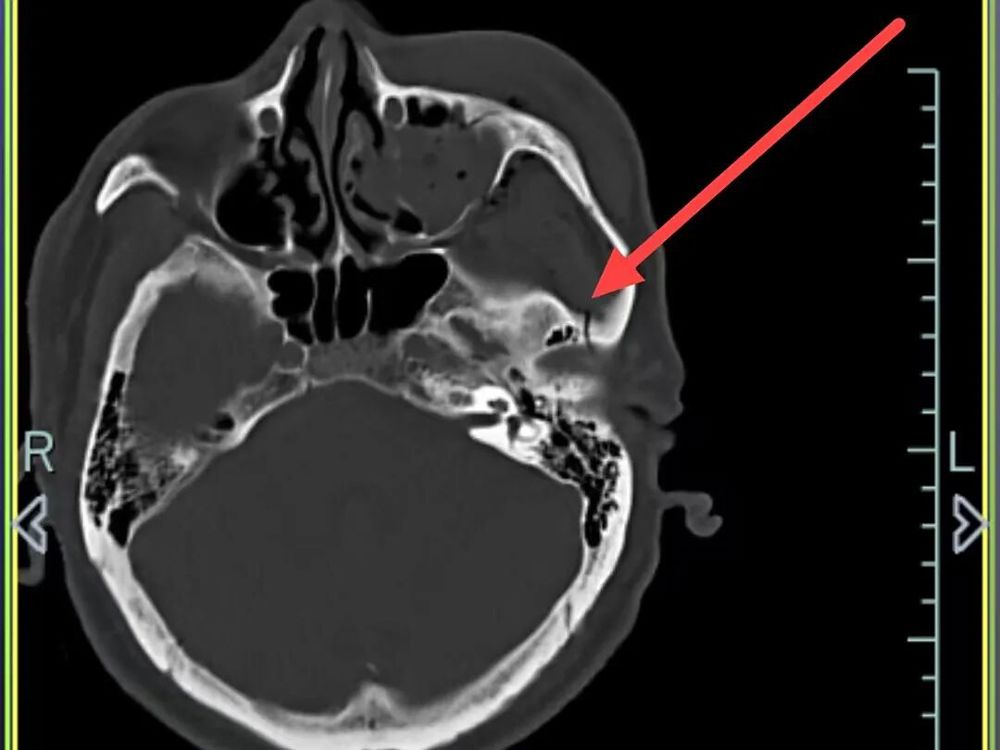

外侧壁、左眼眶外侧壁骨折、左侧颌面部软组织肿胀,软组织内积气

左侧颞骨、左侧颧弓、左侧上颌窦前壁骨折